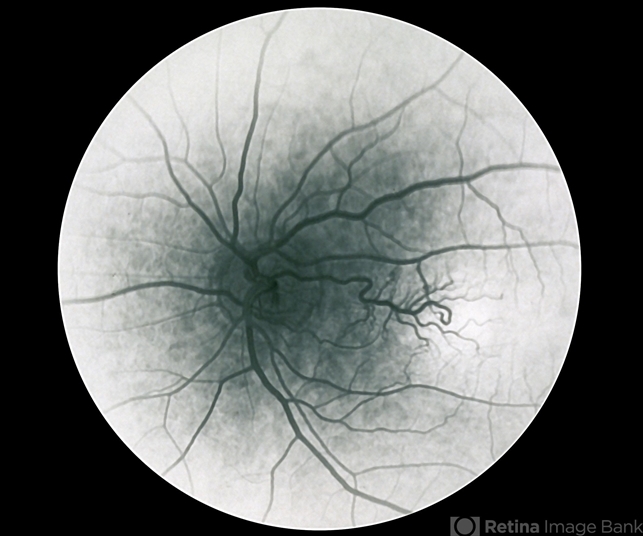

- Congenital retinal macrovessel

- Congenital retinal macrovessel, left eye - fluorescein angiogram (note: this is a scanned negative film FA)